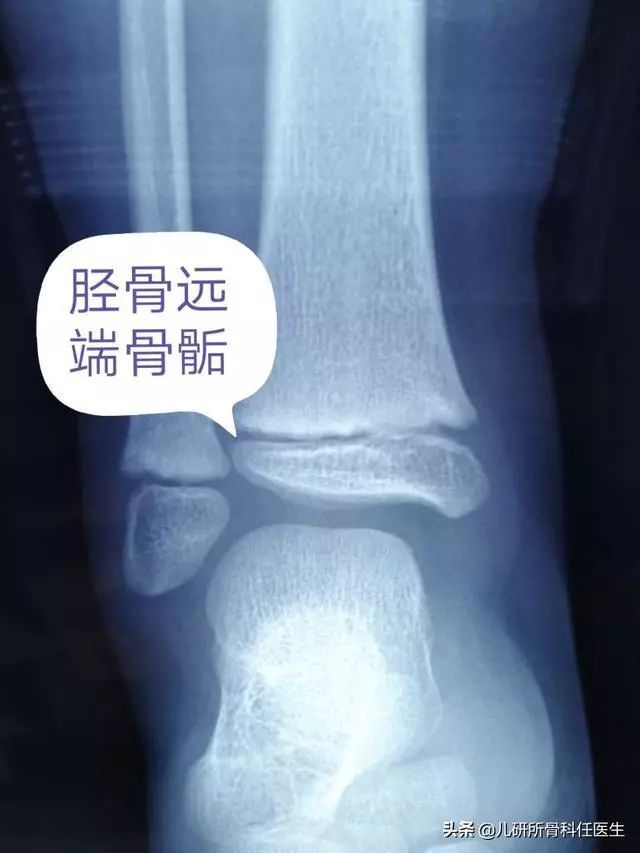

通过阅读相关科普文章,大家都知道适当的体育锻炼是促进孩子长高的重要方法。体育锻炼不仅可以促进骨骼的血液循环,还可以增强骨骼的强度,同时,户外的体育锻炼可以增加皮肤直接接受紫外线照射的量,增加维生素D的形成,都可以促进宝宝的长高。由于宝宝的奔跑运动速度比较快,又缺乏自我保护意识,运动中就很容易受伤。如果是四肢软组织的损伤,临床也叫挫伤,主要就可以通过制动,局部用药和理疗得到缓解。一旦出现累及骨骺的损伤,那就会不可避免的影响长高,严重的还会引起骨骼发育的畸形。从解剖学的角度来分析,四肢长骨的骨骺部位为骨骼最为脆弱的地方,也经常是应力的集中点,运动伤引起骨骺损伤的也不在少数。